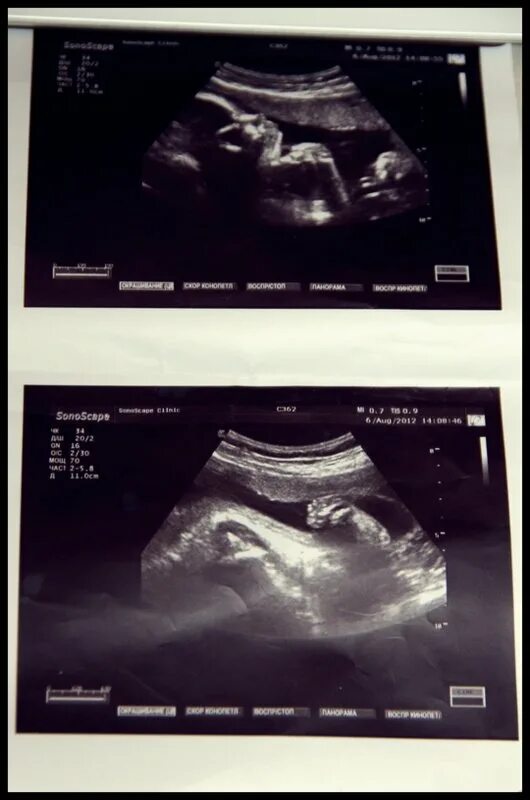

25 недель 2 дня